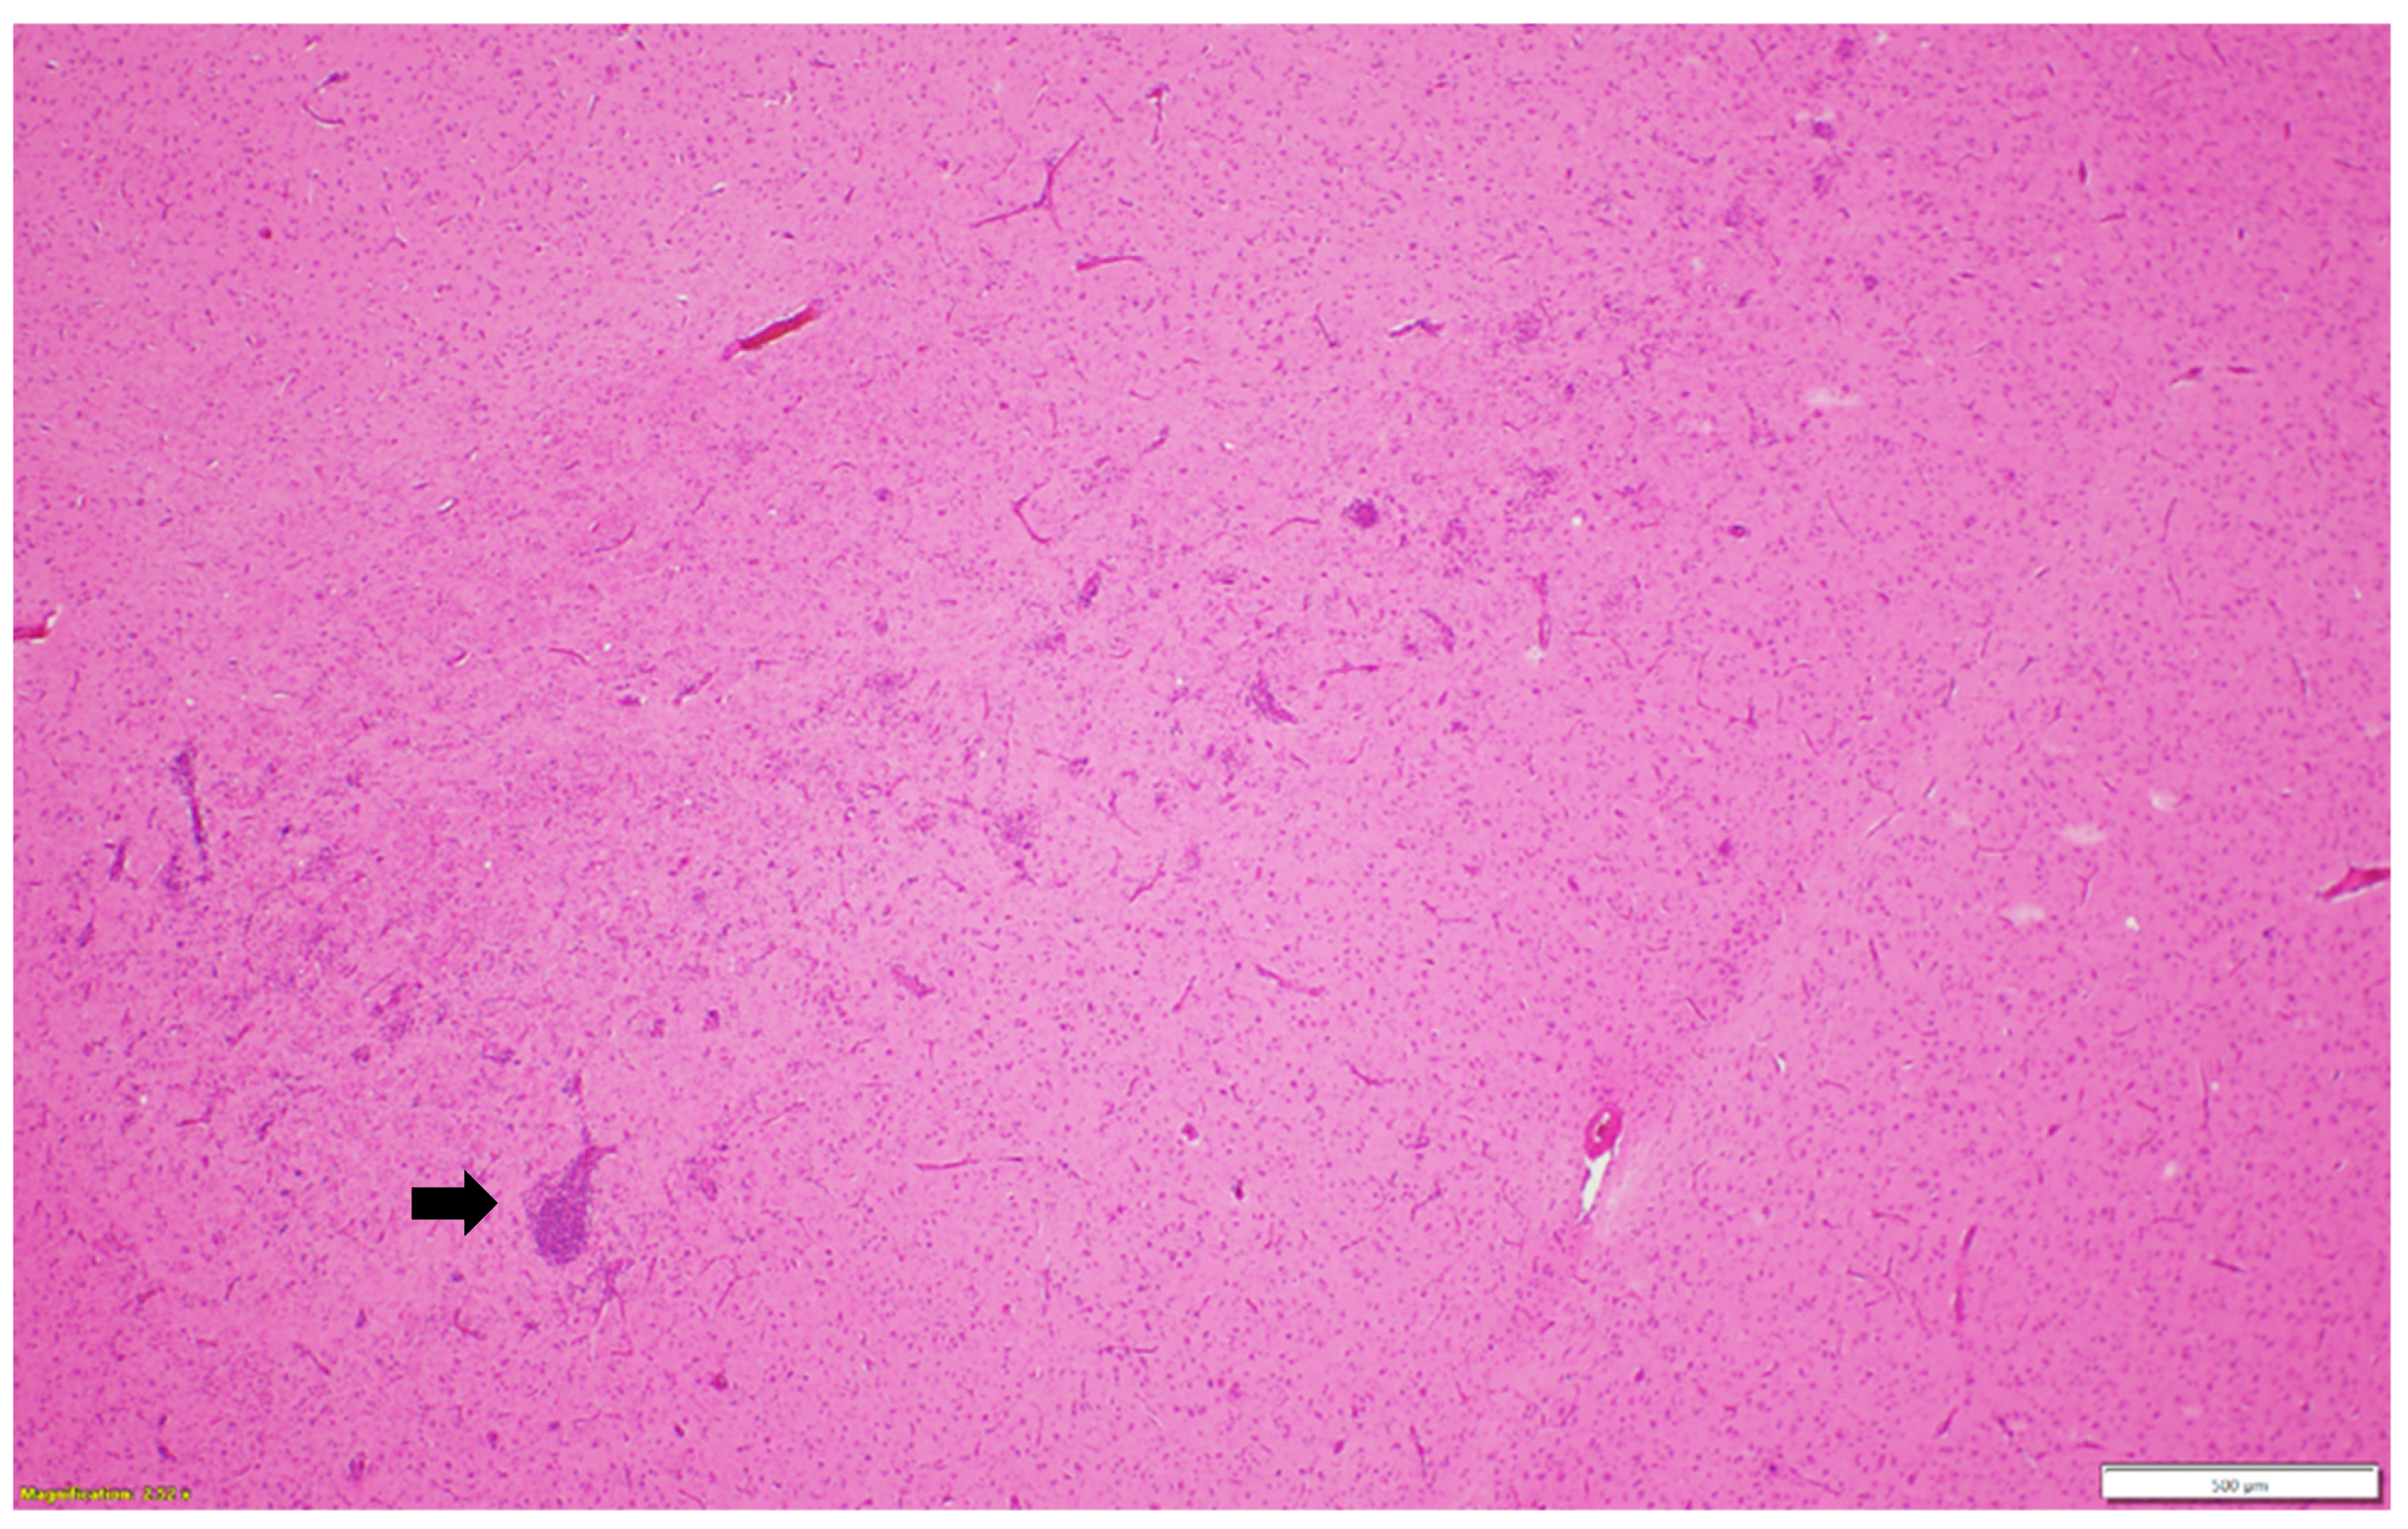

Microscopic examination of different brain, spinal cord, peripheral nerves, and ganglions sections revealed multifocal areas of lymphoplasmacytic and histiocytic infiltrates, indicating encephalitis (Figure 1) in the cerebral white matter, thalamus, hippocampus, and medulla oblongata close the ventricular space. The inflammatory cells around the vessels (perivascular cuffing) as well as around the neurons (satellitosis and neuronophagia) resulted in several neuronal degeneration and central chromatolysis (Figure 2). The gray matter in the spinal cord had multifocal lymphoplasmacytic infiltrates, indicating myelitis (Figure 3). In addition, there was mild to moderate multifocal ganglioneuritis in the pelvis ganglions (Figure 4).

Figure 1.

Multifocal lymphoplasmacytic encephalitis and perivascular cuffing (black arrow) in the cerebral white matter. Paraffin-embedded tissue was stained with hematoxylin and eosin.